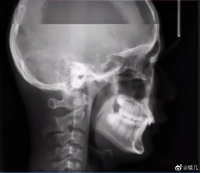

拍牙片時打了個哈欠,變成了毒液?用3D打印技術制作牙齒的好處

小編看到牙片表示:恐怖片果然來源于生活。有網友會問3D打印技術能制作牙齒嗎?小編告訴你:可以!那么用3D打印技術做牙齒有哪些好處呢?